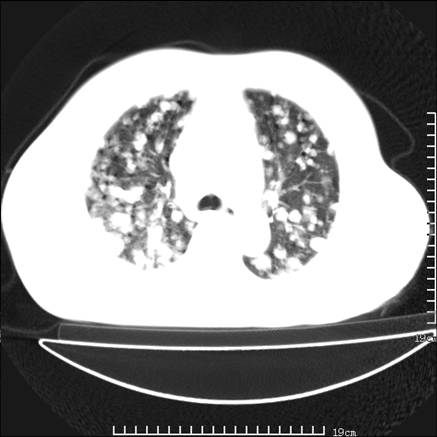

张男,75岁,干咳半年余,小便不利二年,b超检查前列腺增大,未见明显肿块;前列腺癌血生化检查多项指标明显增高。

双肺内多发转移瘤,纵膈淋巴结转移。来源前列腺?建议盆腔mri进一步检查。

双肺转移满了。

两肺广泛转移瘤。